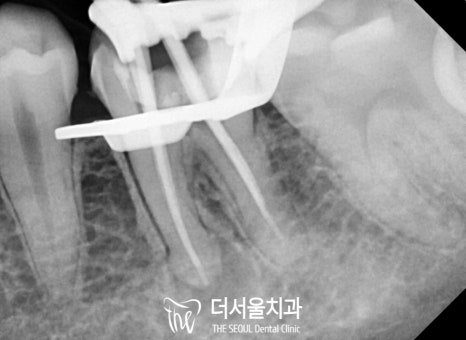

“ 신중하고 꼼꼼하게 ”

한번 진료를 받았던 곳을

또다시 리엔도로 살린다는 게..

생각보다 정말 어려운 일입니다.

채워져 있는 충전재를 제거하는 것부터

정말 신중하고 꼼꼼하게 해야 되는데요.

성남 치과 에서는

한 번에, 확실한 개선을 돕기 위해

세척부터 충전 과정까지

신중하게 도와드렸습니다.